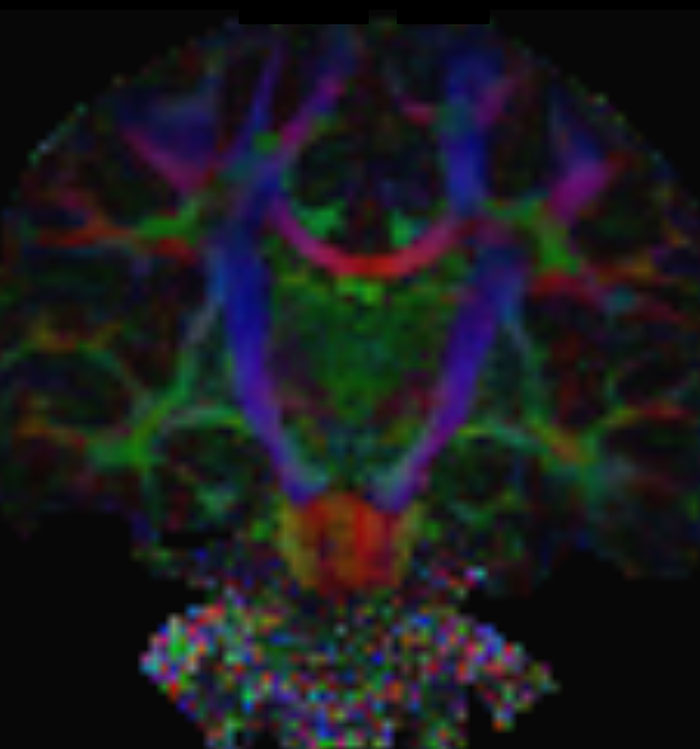

These images are produced using the ABCD protocol and illustrate the use of more sophisticated and accurate models of diffusion. The color FA maps are shown for reference. The diffusion tensor model represents the diffusion within each voxel as an ellipsoid.

Alternative models, such as constrained spherical deconvolution, better capture the rich information available with the use of high b-value dMRI and many sampling directions. In much of the brain, voxels contain multiple white matter tracts, and it is essential to capture this information to be able to perform accurate tractography and generate diffusion connectomes.

Diffusion acquisition on Achieva 3.0T dStream with matrix 140x141, 81 slices, FOV 240x240 mm, voxels 1.7x1.7x1.7 mm, TR 5300 ms, TE 89 ms, flip angle 78, MultiBand SENSE factor 3, partial Fourier 0.645, 102 diffusion directions, b-values 0 (6), 500 (6), 1000 (15), 2000 (15), 3000 (60) , scan time 2x 4:37 min. Images provided by Dr. Watts.

Emotional n-back task combines a test of working memory with the use of emotive (faces) and neutral (places) images. The contrast in the images is between the activity when faces are presented compared to places, showing activation in the amygdala, fusiform, and occipital face areas.

Processing based on the Human Connectome Project (HCP) pipelines. The high resolution of the fMRI data allows extraction of the cortical surface, with minimal averaging of non-cortical signal. Surface based analysis provides improved cross-subject alignment, and prevents signal contamination between adjacent sulci.

Group analysis of 88 9- and 10-year olds part of ABCD, all scanned at UVM on Philips Achieva 3.0T dStream. Scale runs from red p=0.001 to yellow p<10ˆ-5. Images provided by Dr. Watts.

Acquisition using the ABCD protocol for fMRI with TR 800 ms, TE 30 ms, flip angle 52°, 2.4 mm isotropic imaging resolution with a 216×216×144 mm3 field of view using a MultiBand acceleration factor of 6 (60 slices, no gap). Two runs of 5 minutes per subject.